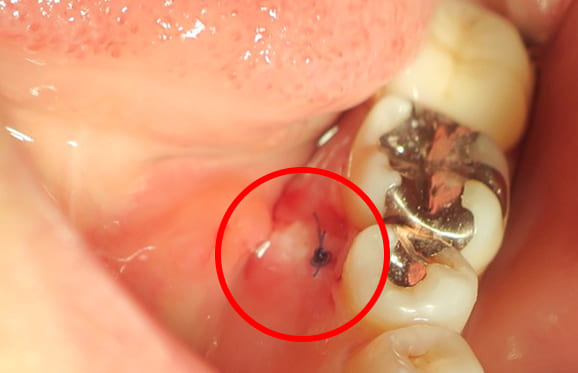

● 症例1

01 左下7の近心根にエンジンファイルの破折

02 ファイル除去時

※根尖周囲の透過像はまだ残存

03 最終の根充剤を充填

※根尖透過像が小さく治癒方向へ向かっている